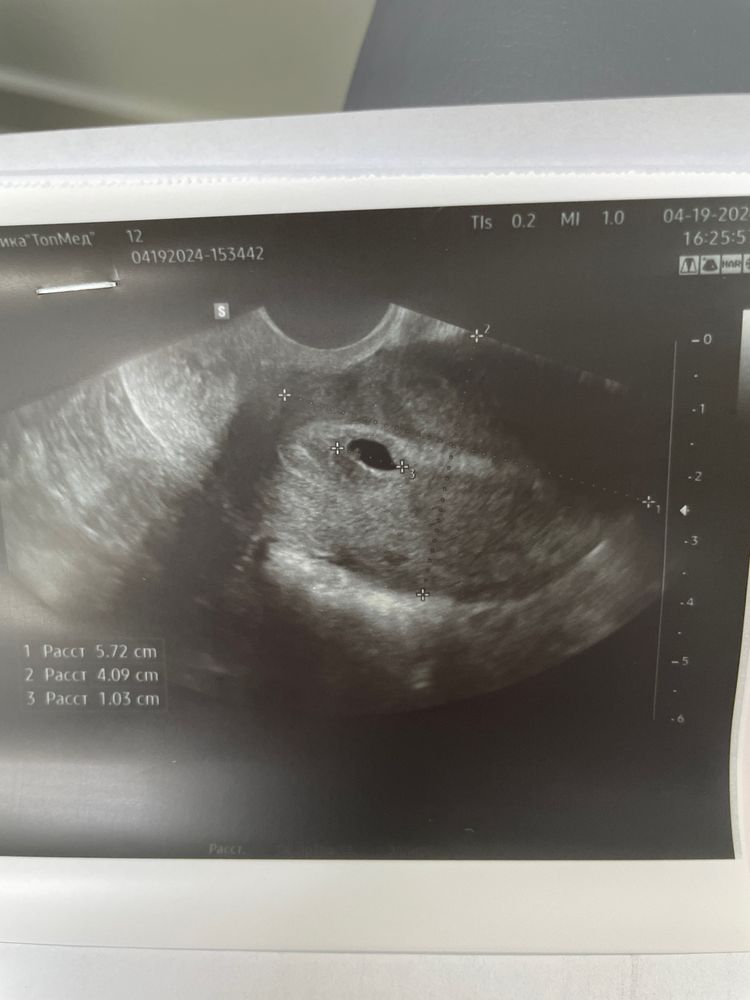

Всем привет. Сегодня у меня ровно 6 акушерских недель. И я проснулась от боли внизу живота. Постепенно начало мазать, потом мазня начала алеть, потом и вовсе вышел сгусток( я ноги в руки и на узи. Ни на что особо не надеясь. Но крошечка на месте, у него даже есть желточный мешочек. Почему кровь - неясно. Врач назначила поддержку и кровоостанавливающее. По узи поставили срок 4 недели. Лежу, уговариваю, чтобы остался со мной 🙏